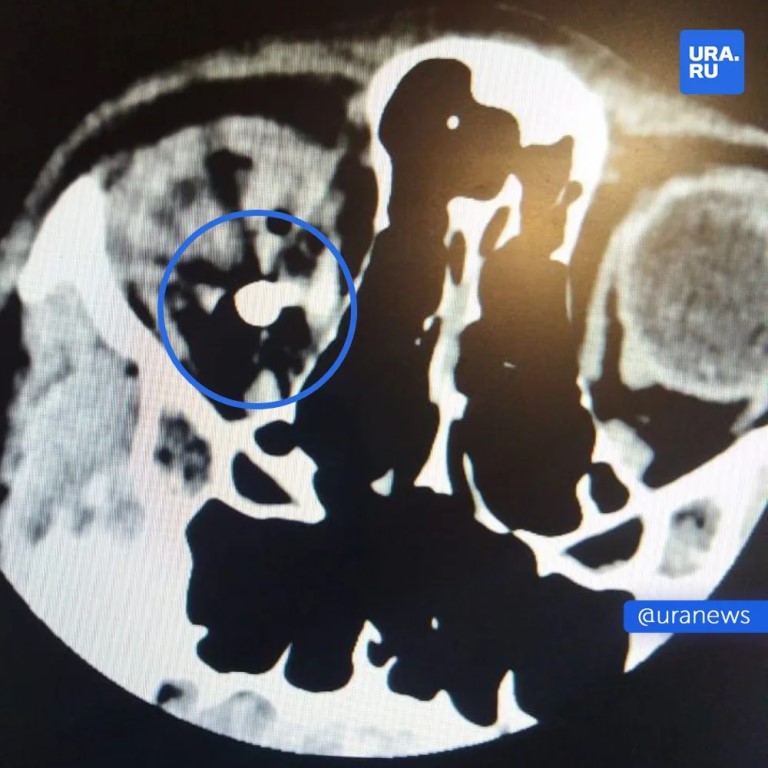

Фото 13-летний подросток из Башкирии выстрелил другу в глаз из пневматики — врачи до сих пор не могут достать пулю из головы. Стерлитамакские школьники играли с оружием, и забава закончилась трагедией — один из них нажал на курок. Пуля пробила глаз и застряла в голове — врачи из Уфы до сих пор пытаются ее извлечь. По данным полиции, пневматическое оружие нашли, как и стрелка. Родители пострадавшего требуют возбудить уголовное дело. МАХ для всего, для новостей — URA.RU